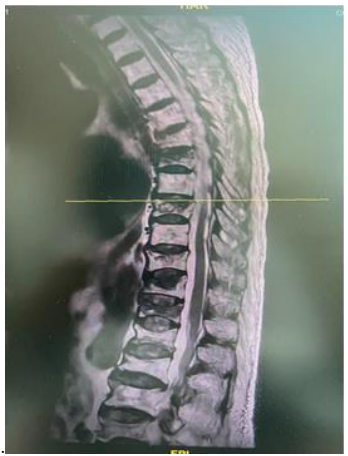

For ESP block , a linear high frequency transducer (Fujifilm, Arette, Germany) was prepped in a sterile fashion and right T7 transverse process was visualized in a longitudinal manner. 17 G epidural Tuohy needle was inserted in plane from cephalo - caudal manner till the tip of the needle touched the Transverse process of T7. (Fig 4,5)The ESP was distended with 10 ml Normal saline followed by 15 ml 0.25 % bupivacaine and 25 mcg Fentanyl. 18 g Epidural catheter was then inserted in to the plane and fixed at 13 cm and connected with an elastometric pump (230 ml 0.2% Ropivacaine and 200 mcg Fentanyl) for three days at a rate of 4-6 ml per hour infusion through the catheter. His immediate NRS scores were 1/10.

Fig 4 Tuohy needle insertion for ESP block at T7

Fig 5 In plane needle insertion at T7 TP. * represents ESP